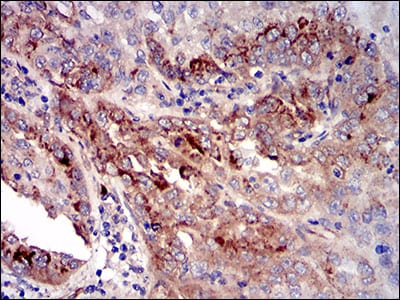

分类: 科研抗体货号: 30545别名: MN; CAIX应用: WB,IHC反应种属: Human